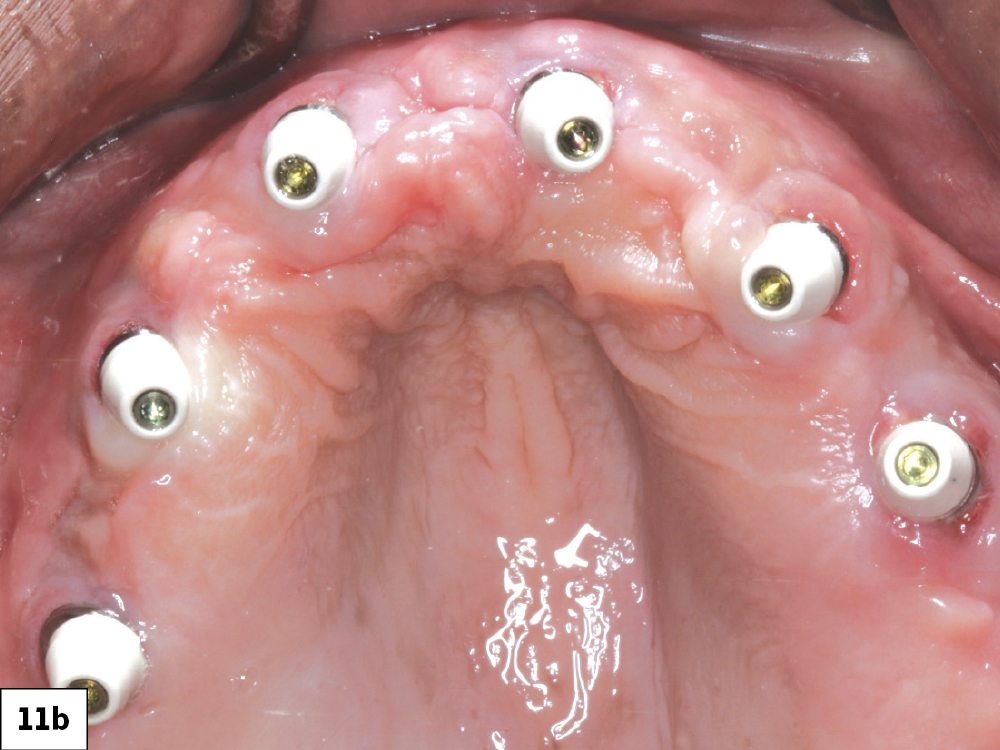

Figures 11a, 11b: A wax rim was tried in and adjusted to determine the appropriate vertical dimension. I then threaded multi-unit abutment (MUA) healing caps over the MUAs for the patient’s comfort and added retention of the transitional complete denture.